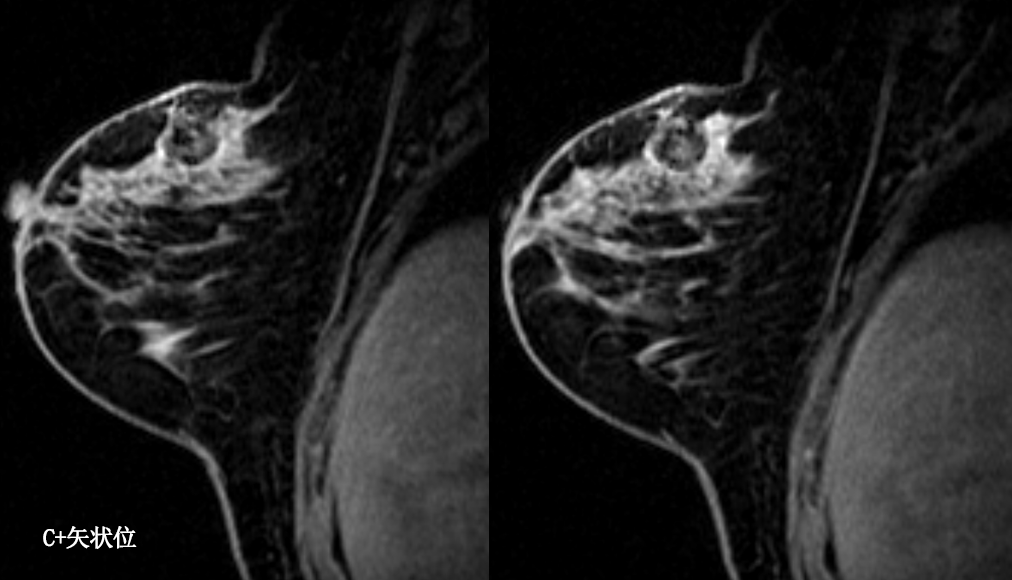

乳腺炎:包括急、慢性乳腺炎和乳腺脓肿,多见于产后哺乳期妇女,急性乳腺炎常有典型的临床症状-红、肿、热、痛;若治疗不及时可形成慢性乳腺炎或乳腺脓肿。MG 表现片状致密影,边缘模糊,患处皮肤水肿增厚,皮下脂肪层模糊;MRI-T1WI 表现为片状低信号,T2WI 高信号,信号强度不均匀,边缘模糊,皮肤水肿、增厚,增强 MRI 通常表现为轻至中度强化,且以延迟强化为主。